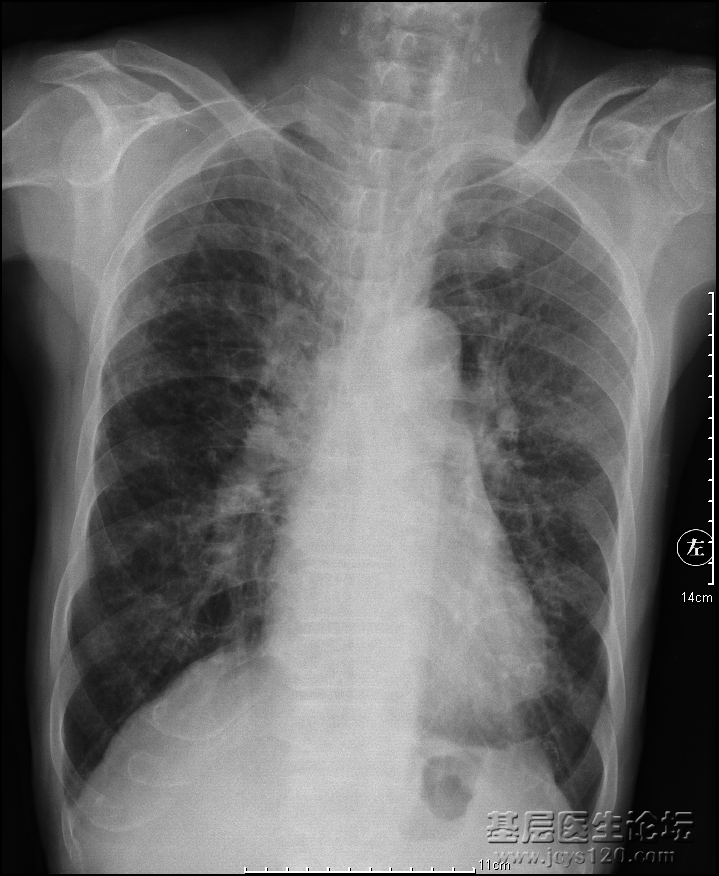

患者男,85岁,咳嗽咳痰,吸烟,余病史未知。 胸部正位 侧位 诊断报告:   两侧胸廓对称,气管上纵隔居中,右侧肺动脉干增粗,双肺纹理增粗紊乱以左肺较为明显,可见大量点片状低密度影呈蜂窝状。主动脉弓迂曲,可见钙化斑,心影大小形态在正常范围。左侧膈面近心尖处可见幕状突起,余膈面光滑,肋膈角锐利。   印象:1.考虑支扩,不除外肺气肿;      2.肺动脉高压;      3.主动脉硬化;      4.局部胸膜粘连。

最后说一下:85岁老人,能活着就已经相当不容易了,自然身体各个方面都有疾病。支气管肺炎是临床诊断,对于老人来说,肺纤维化、支气管扩张更为明显。

支气管扩张的特征不是很明显,慢性间质性感染,肺气肿,右下肺动脉增宽,合并肺心病。建议CT明确肺部感染特征表现(提示支气管扩张也属于感染性病变的一种)